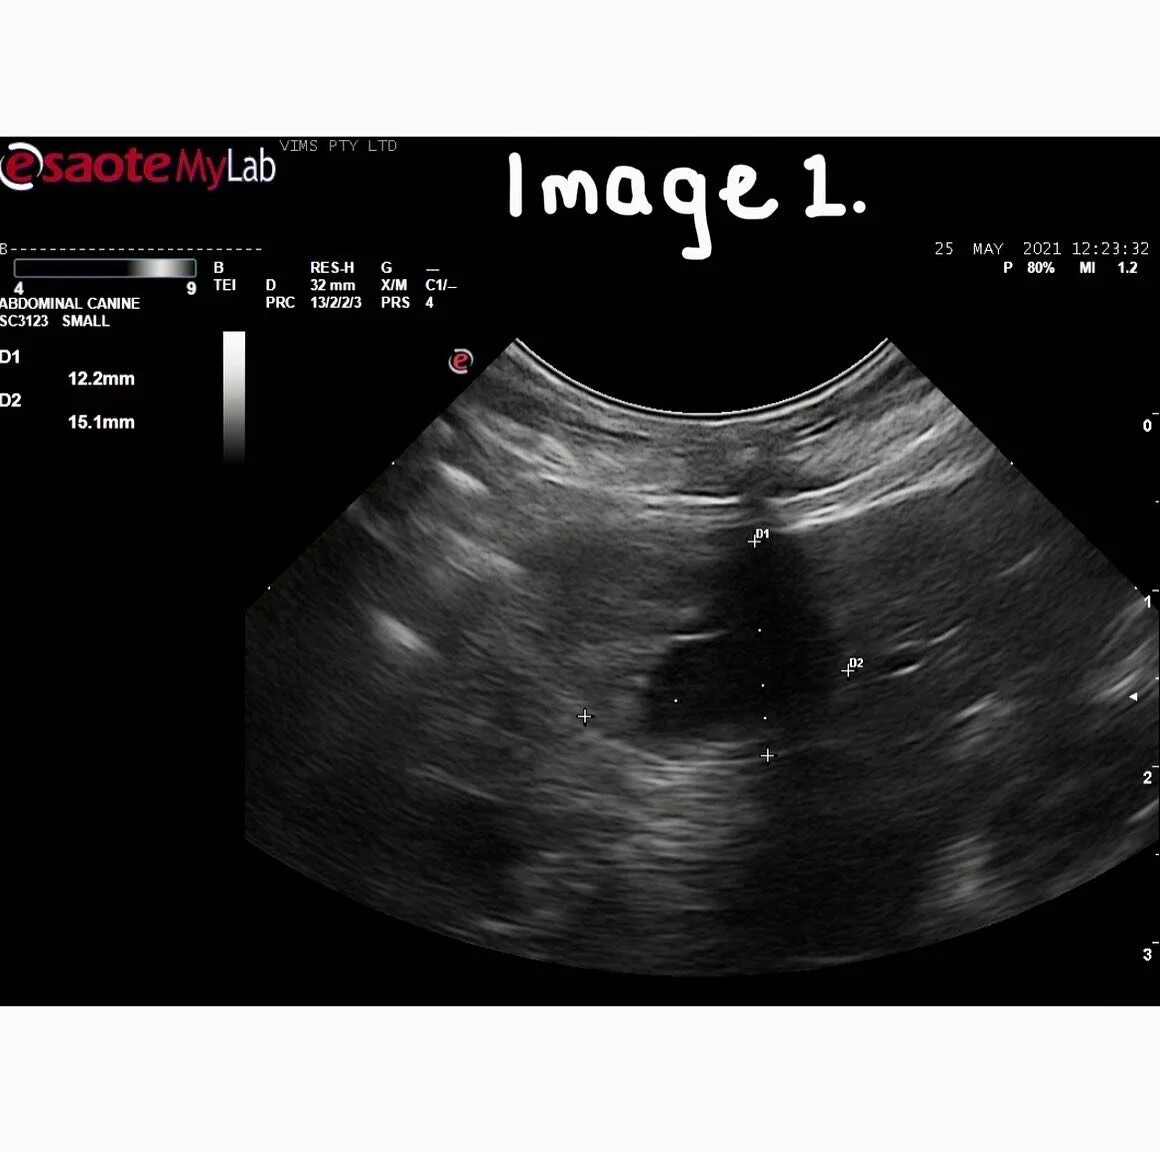

Ultrasound is an invaluable and non-invasive diagnostic test to examine the heart or organs within the abdominal cavity. During the examination, your pet will be lying on his or her side being supported by a nurse. Some patients require sedation for ultrasounds.

If your Pet has had an ultrasound or Echocardiograph, some of their fur will be clipped back to the skin. This is to allow the probe from the ultrasound to work, please see the clip examples below. The majority of patients are given a very mild sedation for ultrasound and not for echocardiograms. A slight sedation helps your pet relax during the procedure which in turn allows us to get the clearest imagine during the scan.